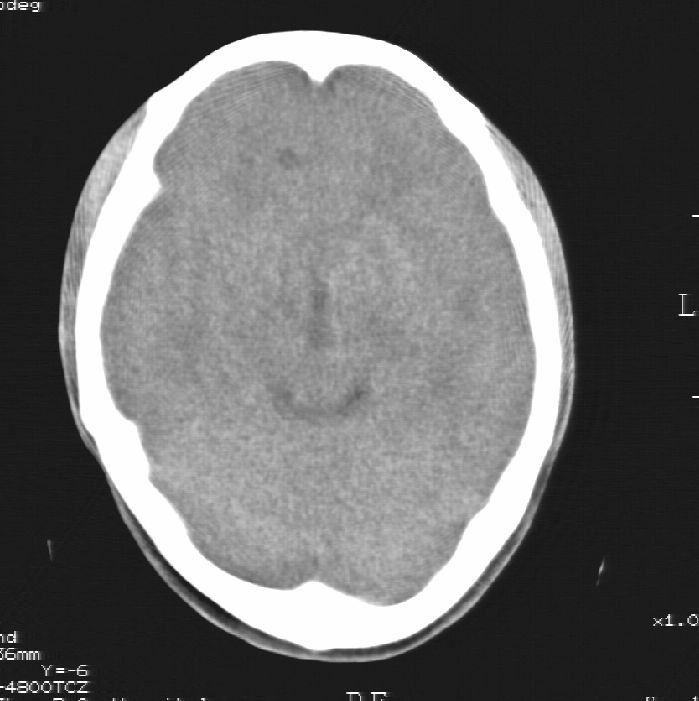

标题: CT25322:脑内发现混杂密度影

患者男,22岁,因外伤入院,低密度影ct值约-120hu。

胼胝体发育不全合并 透明隔缺如 、脂肪瘤。

胼胝体发育不全合并脂肪瘤;建议必要时行mri检查。

脑水肿,头皮下血肿,胼胝体发育不全、合并脂肪瘤及钙化;建议必要时行mri检查。

胼胝体发育不全、合并脂肪瘤及钙化。